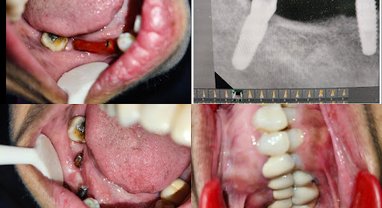

Transform your smile with Full Mouth Dental Implants at Dr. Gupta Dental and Implant Clinic, Greater Noida West. Missing multiple teeth? Loose dentu… Posted on: May 18, 2026